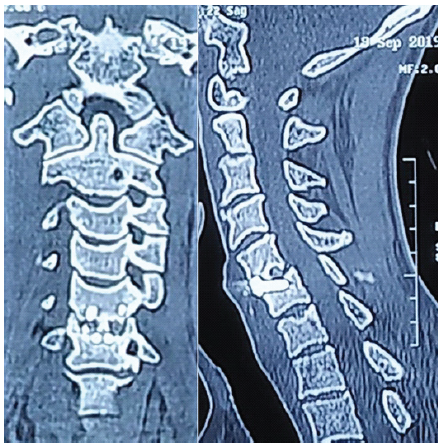

Regarding radiological outcomes (Table 1), the authors evaluated parameters separately for the two implant types used: Group A (PEEK) and Group B (titanium). In Group A, the mean Cobb angle increased from 12.4 ± 9° pre-operatively to 17.3 ± 7.8° post-operatively, stabilizing at 16.4 ± 8° at 1 year. In Group B, the Cobb angle improved from 12.3 ± 6.7° pre-operatively to 17.6 ± 4° post-operatively, settling at 17.1 ± 3.2° after 1 year. Fusion was achieved in 87.5% of cases in Group A and 71.4% of cases in Group B at the 1-year mark (Fig. 4a and b).

Figure 4: (a and b) computed tomography coronal (a) and sagittal (b) images showing signs of additional new bone formation with bony bridging across the disc space indication of fusion.